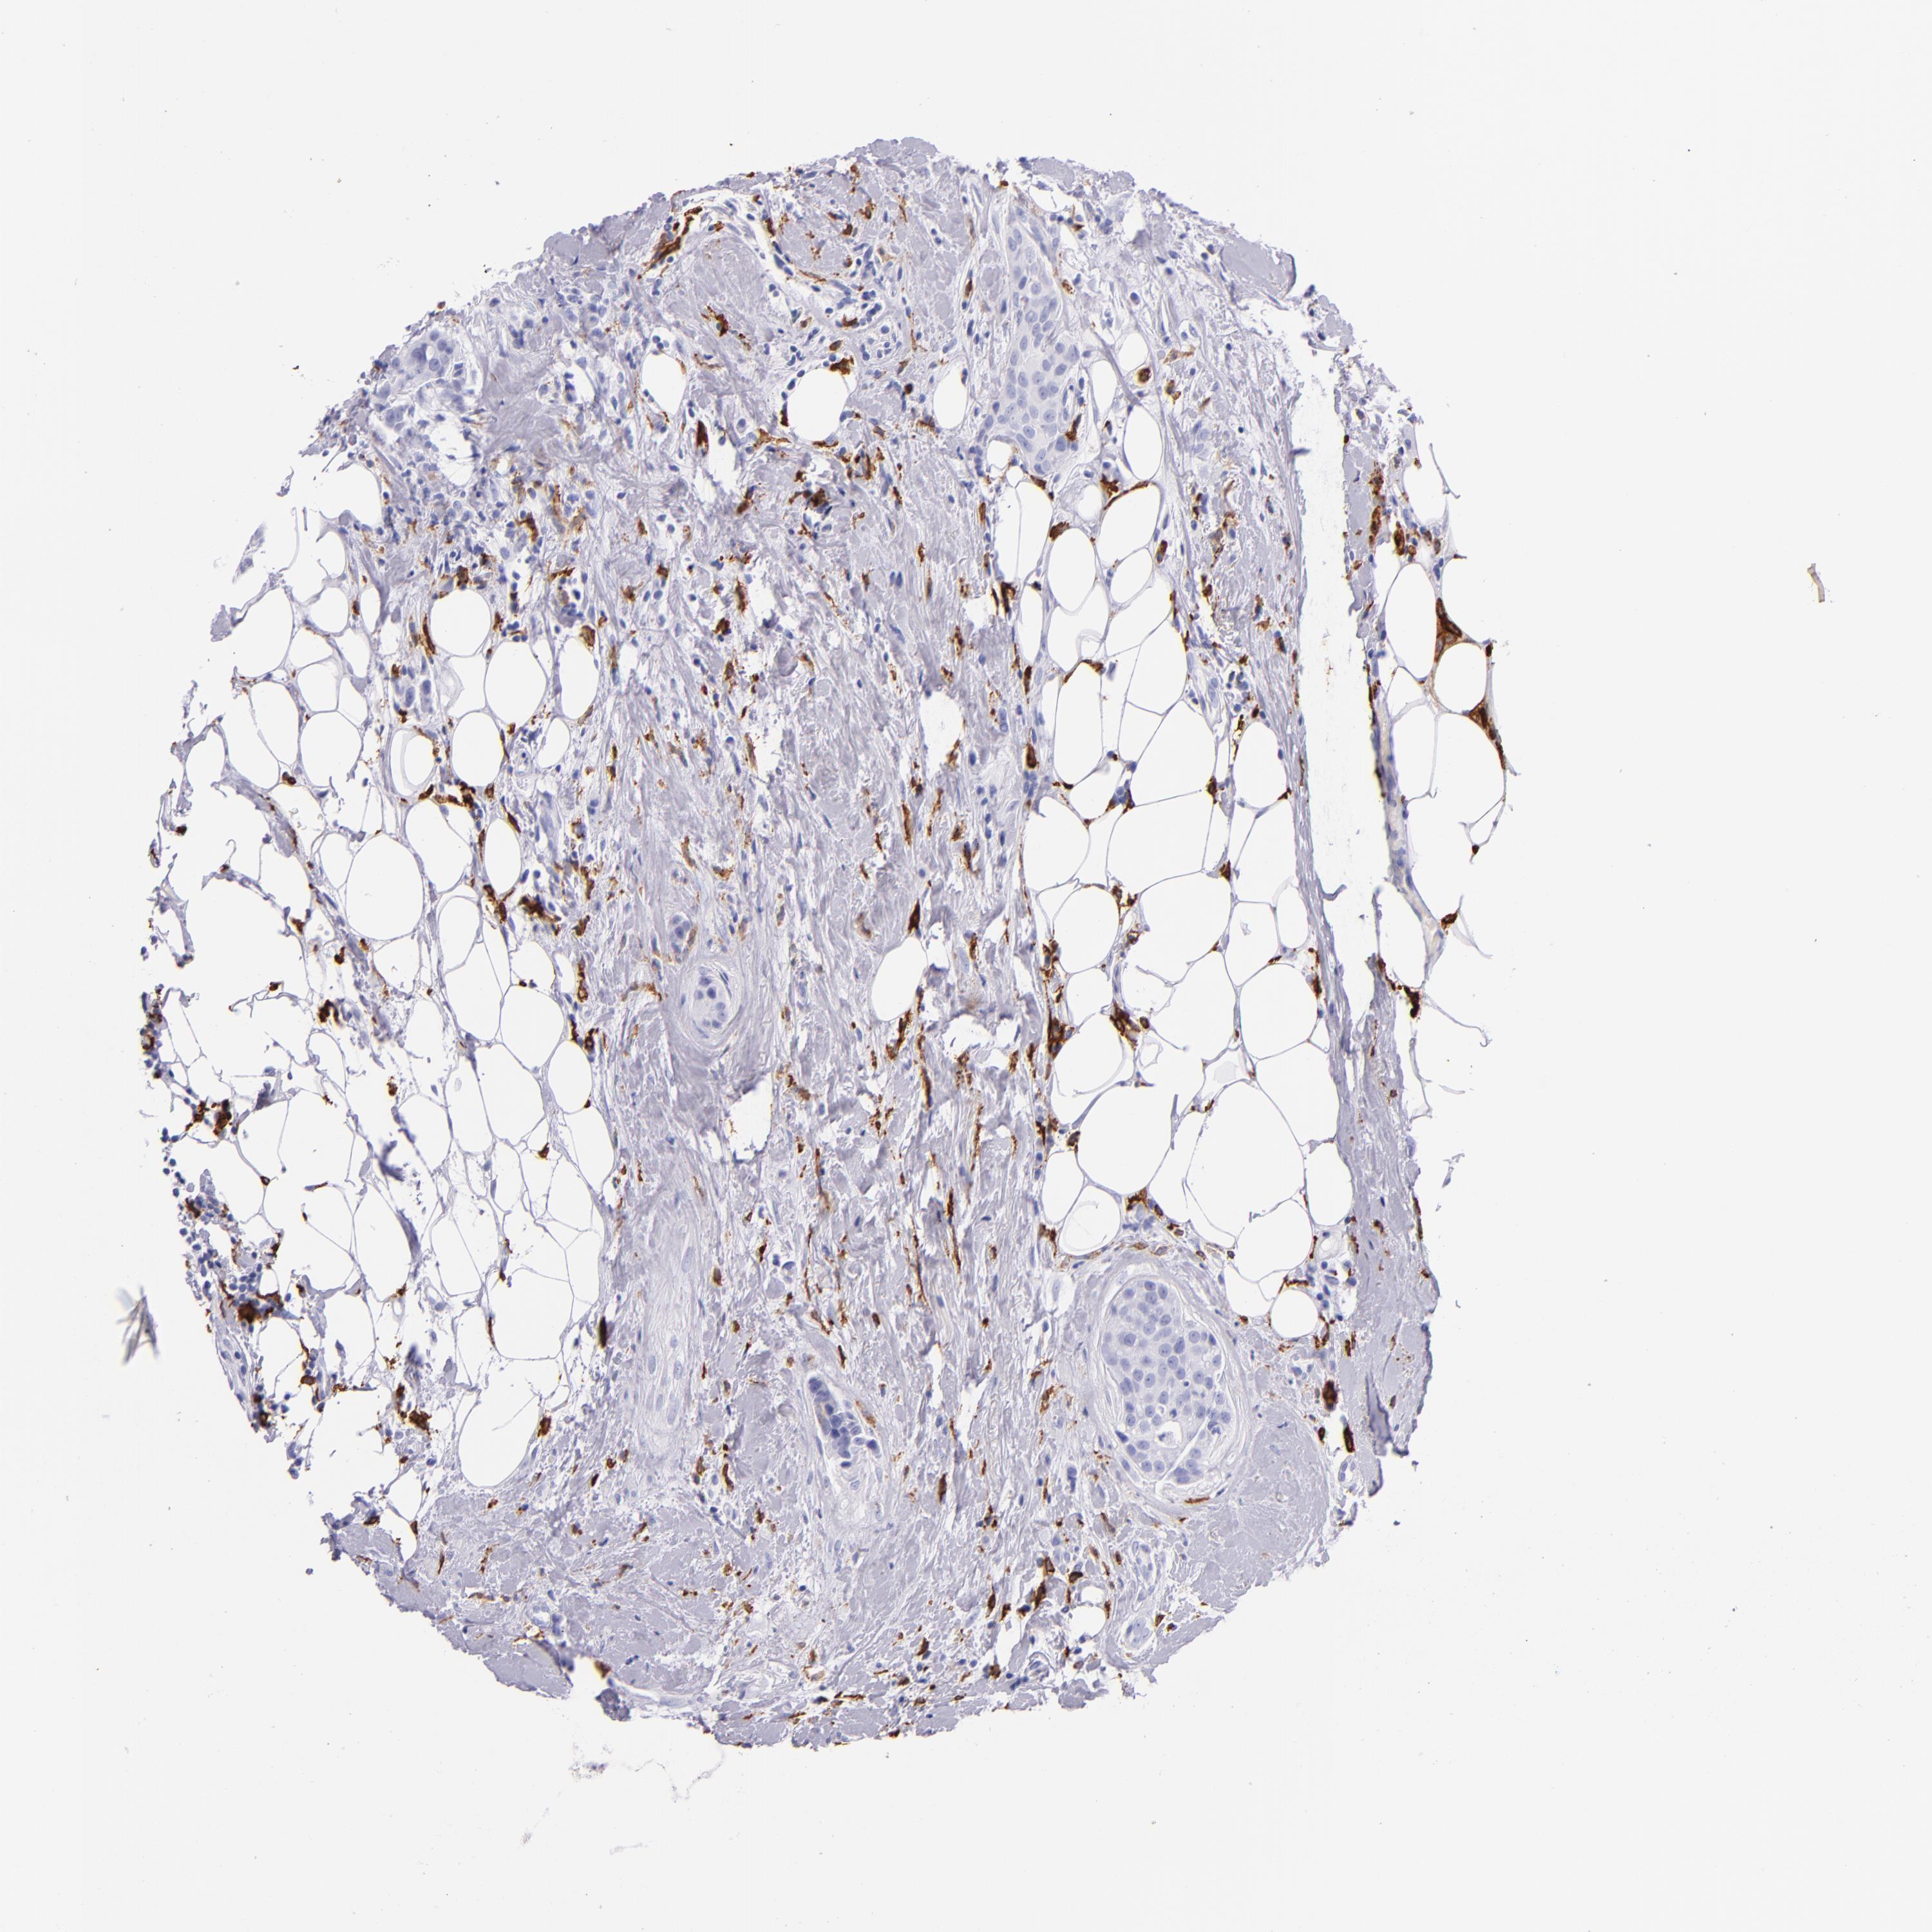

CD163

• CD163